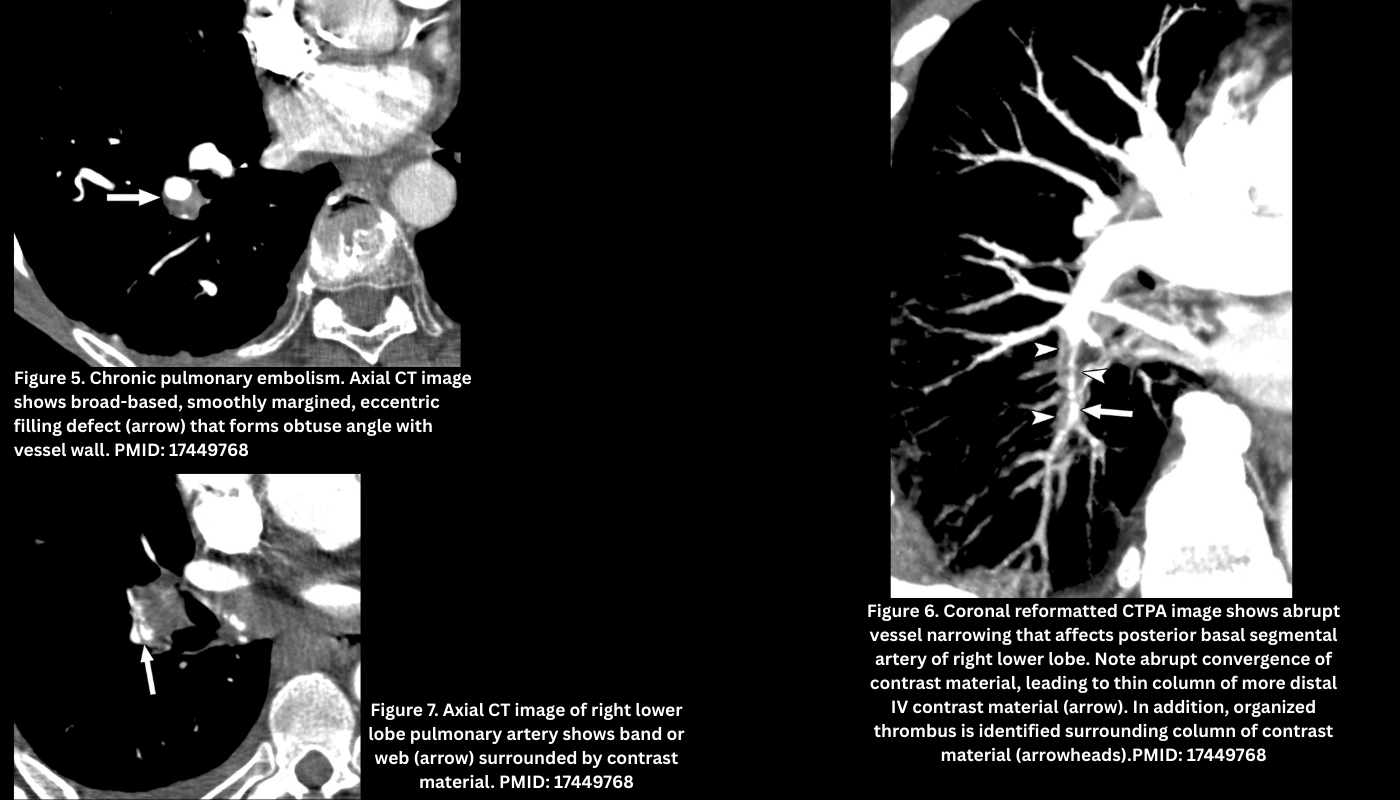

◾️The clot shows signs of organization and recanalization (Below left Figure).

- Webs or bands (thin, linear structures across a vessel).Figure 7.

- Pouch defects (abrupt, concave vessel cut-off with a smaller distal lumen). Figure 6.

◾️The filling defects in CTEPD can be nonocclusive or occlusive.

- Nonocclusive thrombi

- These can appear as linear filling defects that create bands across the pulmonary arteries, which often intertwine to form webs, or as eccentric thrombi forming an obtuse vessel wall margin that may taper into occlusive thrombi more distally (Figure 5).